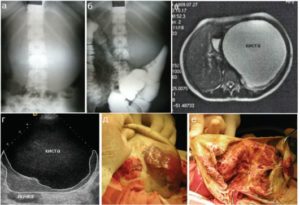

Помимо ультразвукового исследования, применяется:

- КТ – позволяет уточнить локализацию, установить (не на 100%,) тип полости – истинная, ложная или паразитарная, оценить состояние сосудов селезенки, оттесненных опухолью, исключить злокачественный процесс;

- рентген с контрастным веществом – более бюджетная альтернатива КТ.

Лечебная терапия, если диагностирована киста селезенки у ребенка, назначается только после проведения комплексной диагностики. Диагноз ставится на основании данных анамнеза, по результатам УЗИ.

Проводится компьютерная томография, МРТ, ряд лабораторных анализов, аллергические пробы.

При необходимости проводится дифференциальная диагностика, которая позволит отличить кисту в селезенке от злокачественных новообразований в органе.